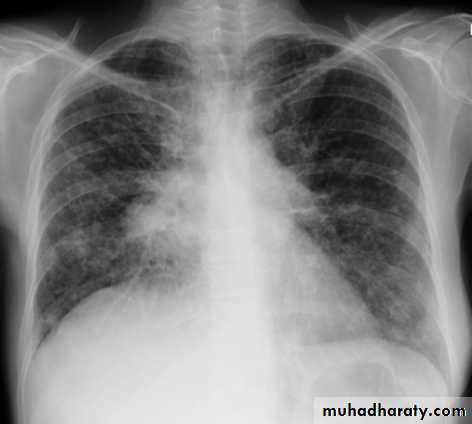

Mediastinal masses are recognized on frontal radiographs by the presence of a soft tissue density that causes obliteration or displacement of the mediastinal contours or interfaces. The lung -mass interface typically is well defined laterally, where it is convex with the adjacent lung, and it creates obtuse angles with the lung at its superior and inferior margins. This latter characteristic is diagnostic of an extrapulmonary lesion, whether intramediastinal or pleural. Lateral displacement of the trachea or heart may be seen with large mediastinal masses, sometimes first recognized by displacement of an indwelling endotracheal tube, nasogastric tube, or intravascular catheter.

Signs of enlarged bronchopulmonary lymph nodes or hilar mass on frontal chest radiographs include : hilar enlargement, increased hilar density, lobulation of the hilar contour, and distortion of central bronchi . An abnormal hilum is most easily appreciated by comparison with the contralateral hilum and by review of prior chest radiographs . An increase in density of the hilar shadow is seen with a hilar mass that lies primarily anterior or posterior to the normal hilar vascular shadows. In such patients, the enlarged hilar nodes will produce an increase in density on frontal views and a lobulated appearance when viewed in profile on a lateral radiograph.When an abnormally dense hilum is noted, the relationship between the vessels and the density must be assessed. A density through which the normal hilar vessels can be seen constitutes a hilum overlay sign, which indicates a mass superimposed on the hilum.